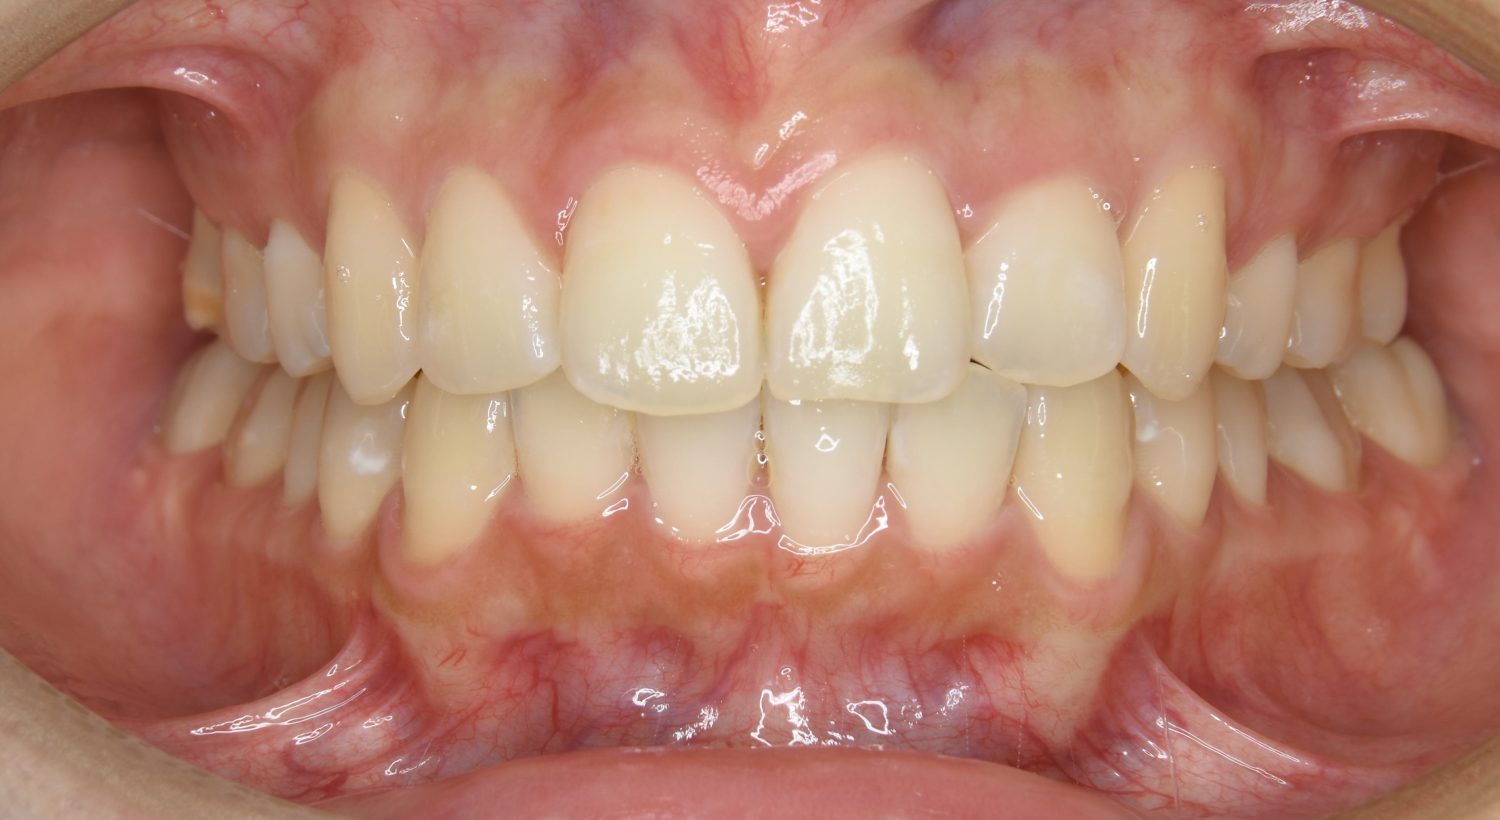

叢生の症例紹介①

Before

After

主訴

前歯のガタガタが気になる。

治療内容

上顎左側第一小臼歯を抜歯し、アライナー(インビザライン)にて治療を行いました。

治療費

1,150,000 円(税込)

治療期間

23ヶ月

通院回数

13回

想定されたリスク

※歯根吸収、歯肉退縮、歯髄壊死、顎関節症状

※アライナー(インビザライン)は日本の薬機法未承認の矯正装置であり、医薬品副作用被害救済制度の対象外となる場合があります。

丸山和宏先生

ピーススマイル矯正歯科

左上の側切歯が完全に内側に入り込んでいる状態でした。左上の第一小臼歯のみ抜歯を行い治療を行うことで機能面および審美面を改善しました。